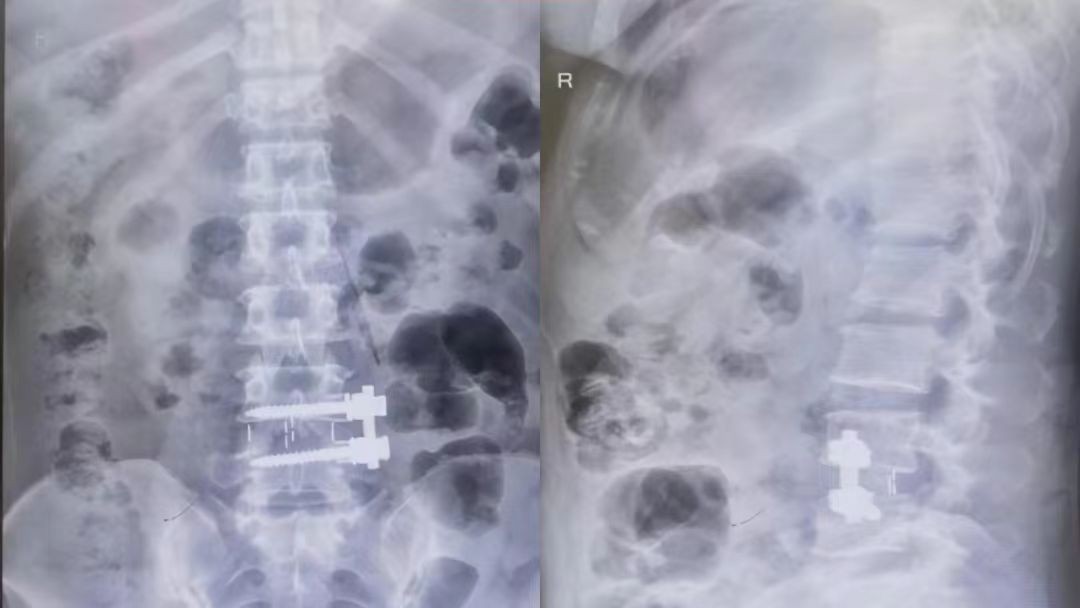

骨科团队经过详细地评估后,决定选择国际先进的OLIF微创技术!手术只在腹部开一个小小的3cm斜切口,精准完成椎间融合,出血量还不到50ml~术后4到6小时,患者就能下地走动,腰腿疼痛明显减轻。患者超开心地说:“恢复也太快了吧!终于可以舒服过日子啦!”

间接减压超稳当:用大号融合器撑开椎间隙,瞬间给神经腾出空间,压力一扫光~还能顺便矫正腰椎歪斜,长久稳定不是梦!